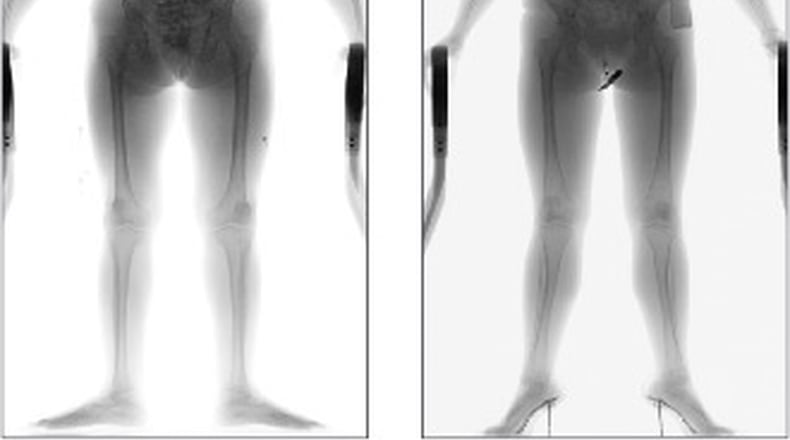

The scanner — able to detect a firearm taped to a body, a needle in a pocket or a small baggie of drugs in an intestine — will be purchased from OD Security North America for $118,750.

Keller said the system is easy to use and safe, resulting in less radiation exposure than sleeping with a partner. Harder is identifying an anomaly off the resulting image.

”It’s not difficult to use the system,” he said. “The learning curve is in learning to read the scans and see the abnormalities in the body where something is being contained.”